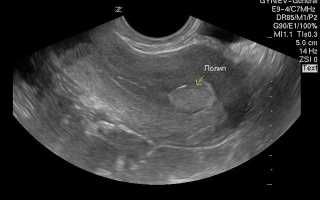

Врачи отмечают, что полипы в матке и эндометрии на УЗИ могут выглядеть как гиперэхогенные образования, которые имеют четкие контуры. Эти образования могут быть одиночными или множественными, и их размеры варьируются от нескольких миллиметров до нескольких сантиметров. При наличии кровотока, что часто определяется с помощью цветного допплеровского картирования, полипы могут демонстрировать усиленное кровоснабжение, что указывает на их активность и потенциальную возможность злокачественного перерождения. Важно, что наличие кровотока не всегда свидетельствует о патологии, однако требует внимательного наблюдения и, при необходимости, дальнейшего обследования. Врачи подчеркивают, что правильная интерпретация УЗИ-данных и комплексный подход к диагностике являются ключевыми для выбора оптимального метода лечения.

Как выглядят полипы на снимке УЗИ?

Ультразвук – это волны, которые при отражении формируют картинку. Жидкости поглощают излучение и являются анэхогенными, выглядят темным пятном. Чем плотнее структура, тем более она эхогенна и светлее. По таким характеристикам можно определить тип ткани, например, кость высвечивается белым и называется гиперэхогенной. Киста с жидким содержимым будет круглым темным пятном с четкими краями.

Некоторые признаки, характеризующие патологию при УЗИ:

- Хорошо различимые границы;

- Грибообразная или круглая структура;

- Полость матки расширена, как и цервикальный канал;

- Деформация контура органа;

- Кисты эндометрия вокруг основания полипа.

Железистые образования, как менее плотные смотрятся более темными, чем фиброзные. По тому, как выглядят полипы эндометрия на снимке, невозможно точно определить их разновидность.

Признаки полипа эндометрия в матке на УЗИ. Полип матки на УЗИ выглядит как новообразование с четким контуром. Другим его признаком может стать расширение полости и утолщение стенки матки. Для диагностики новообразований лучше всего подходят 5-7 дни менструального цикла.